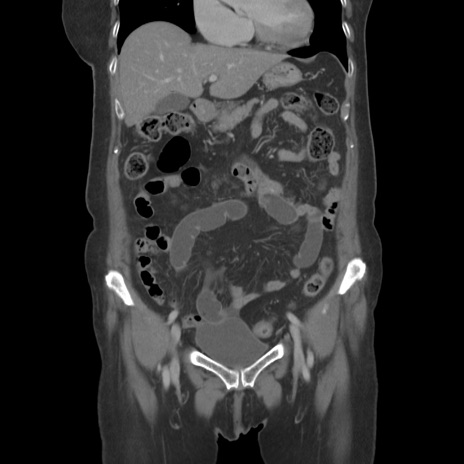

症例19(冠状断像)

【症例】80歳代女性

【主訴】下腹部痛

【現病歴】約8時間前より下腹部痛の出現あり、救急外来受診。

【既往歴】両側付属器切除

【身体所見】意識清明、下腹部正中に手術痕あり、その部位に一致して圧痛と反跳痛あり。腸蠕動音は亢進。

【データ】WBC 9300、CRP 0.15